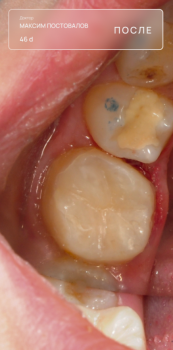

Постовалов Максим Юрьевич

Постовалов Максим Юрьевич принимает в «Стоматологическая клиника ОПТИМА С» в Перми. Стаж 6 лет. Специализируется на терапии, по которой клиника оказывает 8 услуг. Имеет 12 работ до/после в портфолио. Также 32top представляет форму онлайн расписания, через которую можно записаться к специалисту на свободную дату и время.

12 работ в портфолио